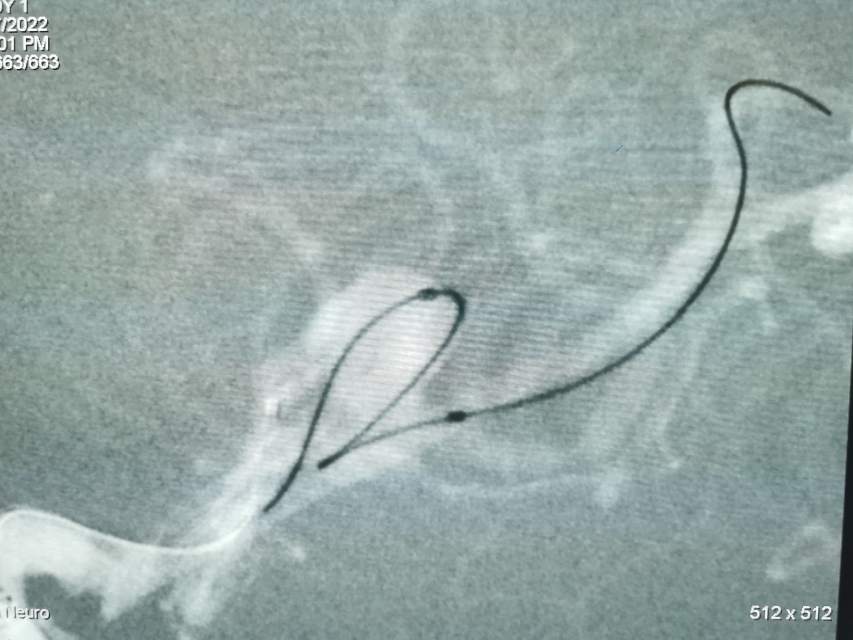

福建中年女性,近期在外查出“颅内动脉瘤”,经推荐转来我院诊治。患者的颈内动脉通路迂曲,动脉瘤也位置奇特,解剖复杂,动脉瘤远近段的血管弯弯绕绕,重重叠叠,眼花缭乱,难以兼顾找到最佳位置。最终克服困难,将“基底型”动脉瘤改变为“侧壁型”动脉瘤,顺利给予治疗……